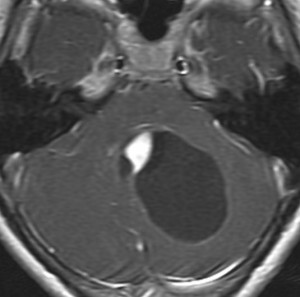

中脳視蓋毛様細胞性星細胞腫 tectal glioma(詳しくはここをクリック)

中脳視蓋グリオーマとして知られるものです。この腫瘍は基本的には,初回手術で全摘出できるのですが,現実的には,技術的に難しすぎるので部分摘出で終えることが多いでしょう。この子は,15歳の時に閉塞性水頭症のために,頭痛,嘔吐,意識障害,瞳孔不同となりました。開頭部分摘出術と第3脳室開窓術で回復して,その後にカルボプラチンとビンクリスチンの化学療法を受けました。でも腫瘍増大が止められずに,発症1年後に54グレイ30分割の放射線治療を受けています。さらにその半年後くらいから再増大しましたが,スードプログレッションと考えられました。のう胞性拡大が止まらず,発症3年後にまた再開頭手術で亜全摘出しました。